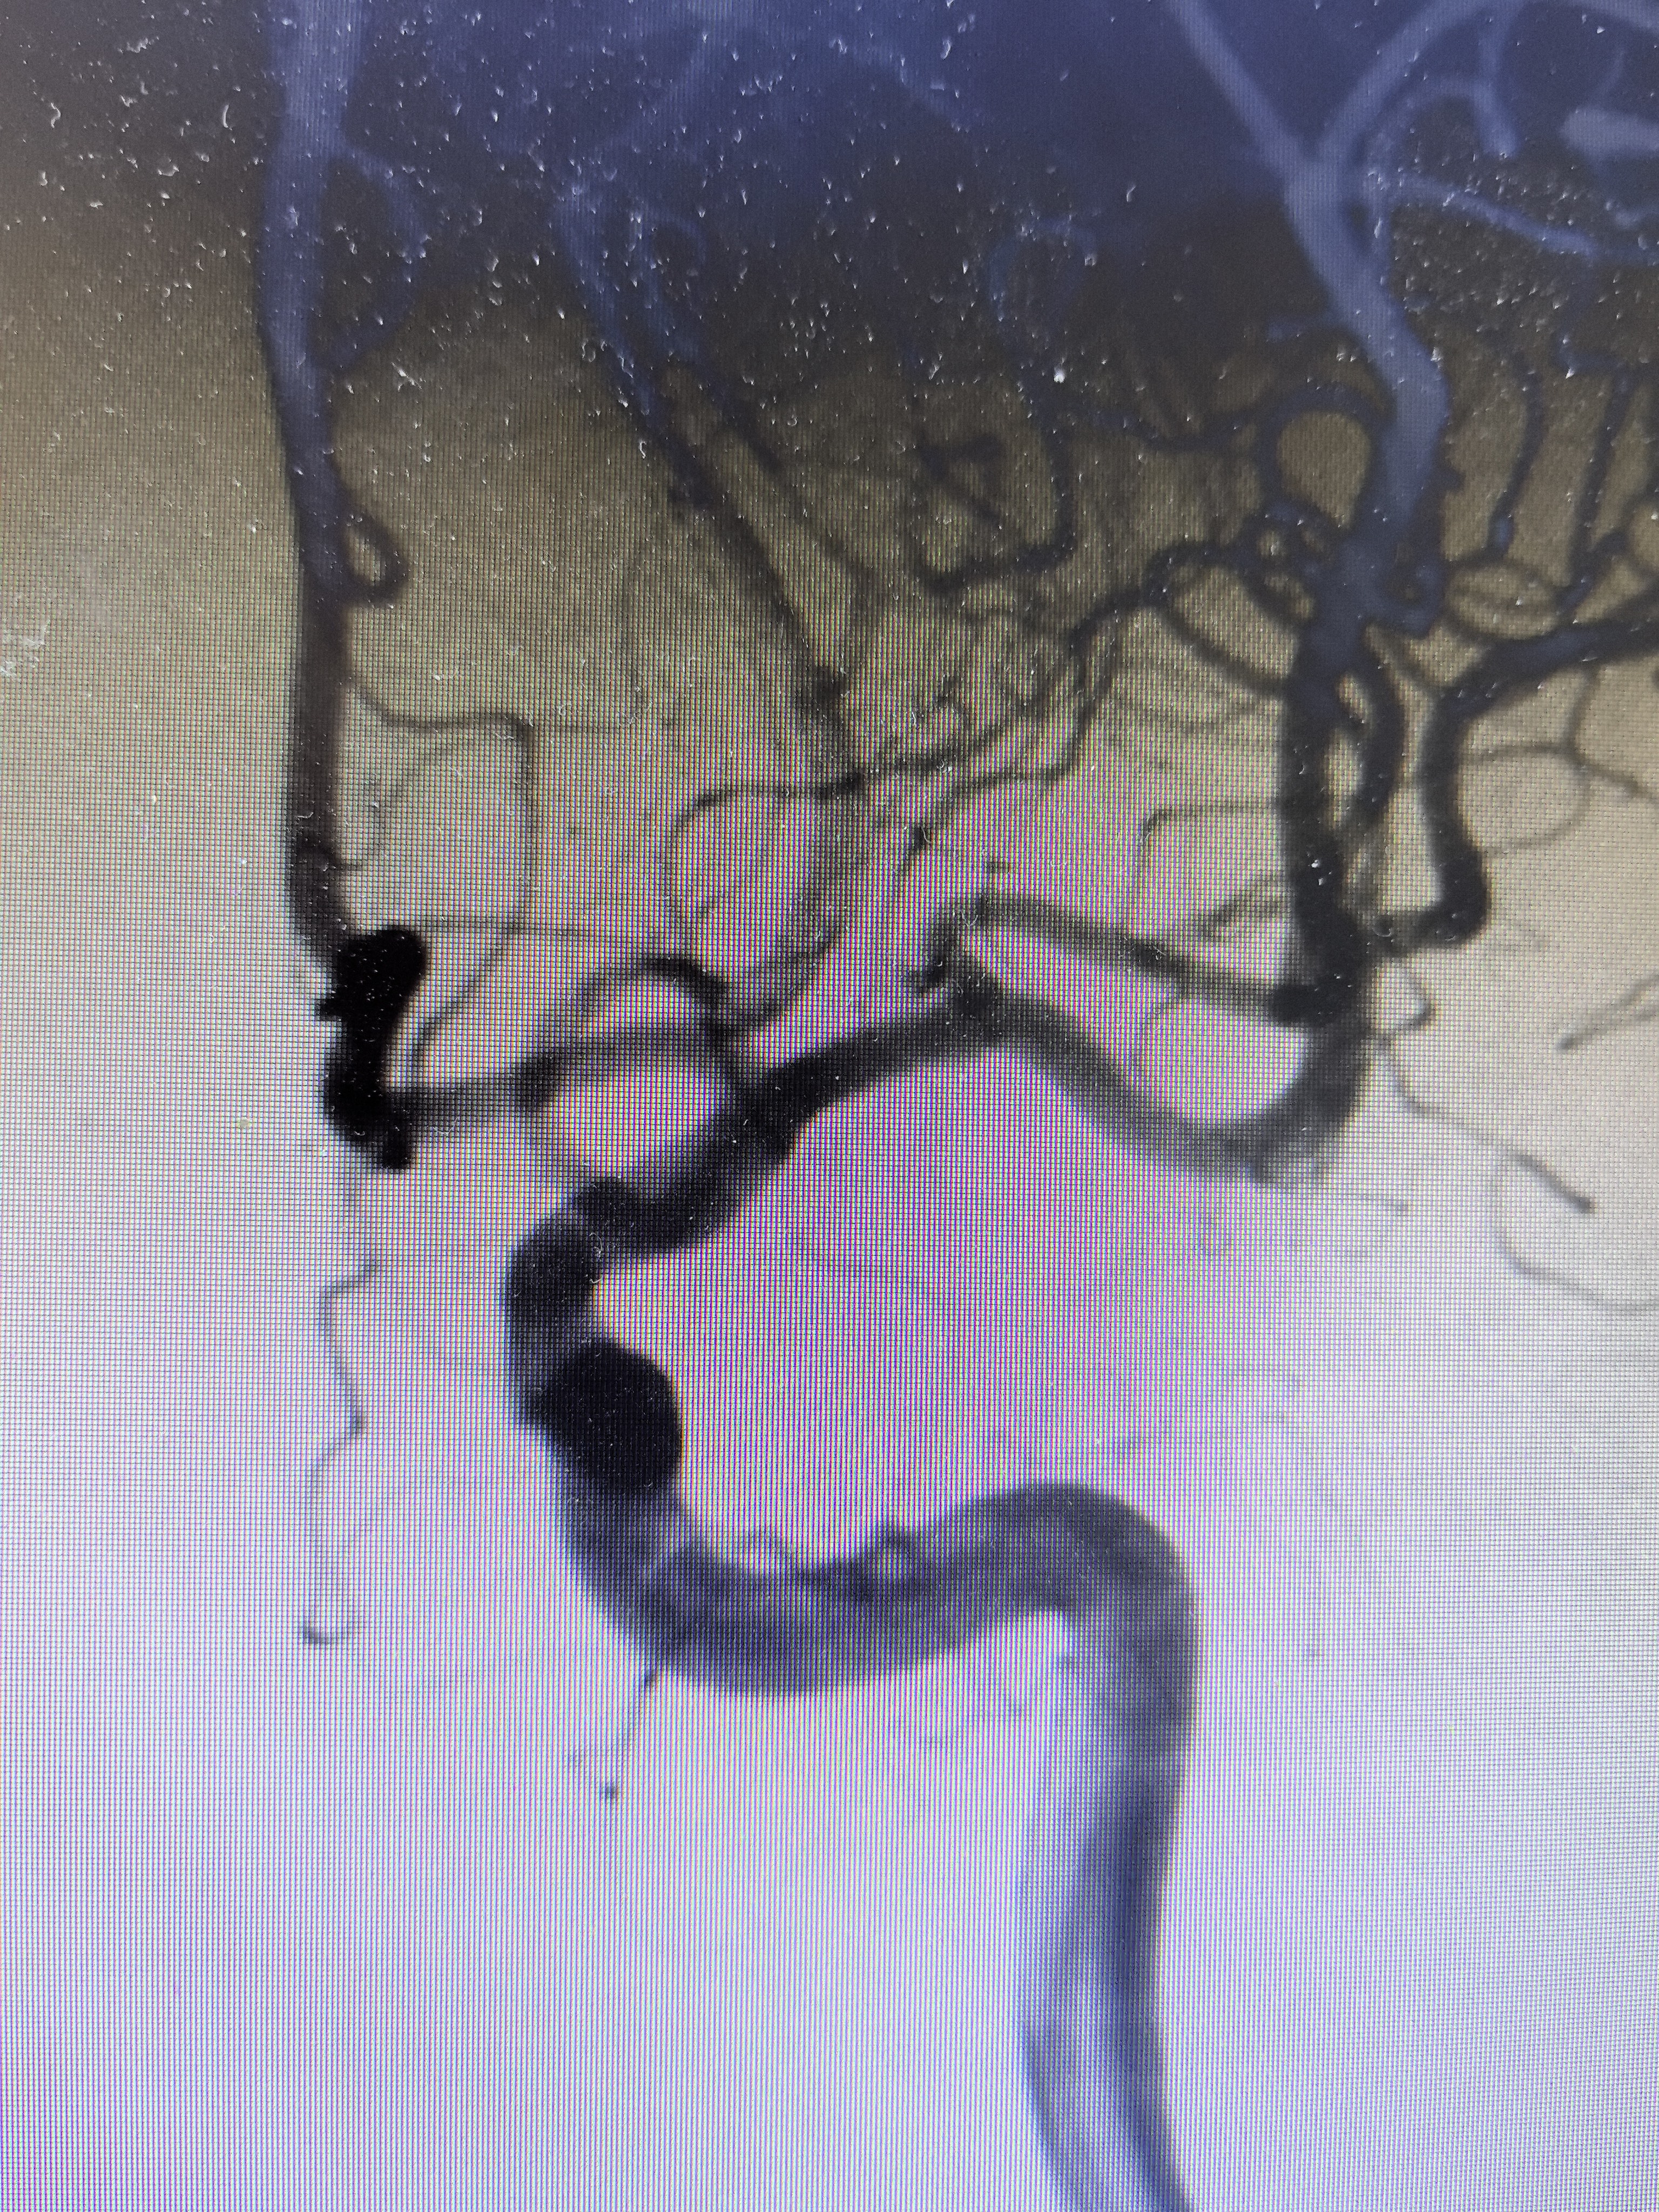

DSA显示左侧变异颞前早期分支起始部微小动脉瘤

路途下显示动脉瘤

0.014微导丝可以进去瘤内,微导管进入瘤内困难

缓慢撤出微导丝,微导管位于瘤颈口尚稳定

完全撤出微导丝,微导管于瘤颈口稳定

弹簧圈尝试栓塞

解脱弹簧圈后微导管弹出

造影显示动脉瘤栓塞满意,术闭。

同期行脑室外引流降颅压,术后1年随访,MRS:0分。